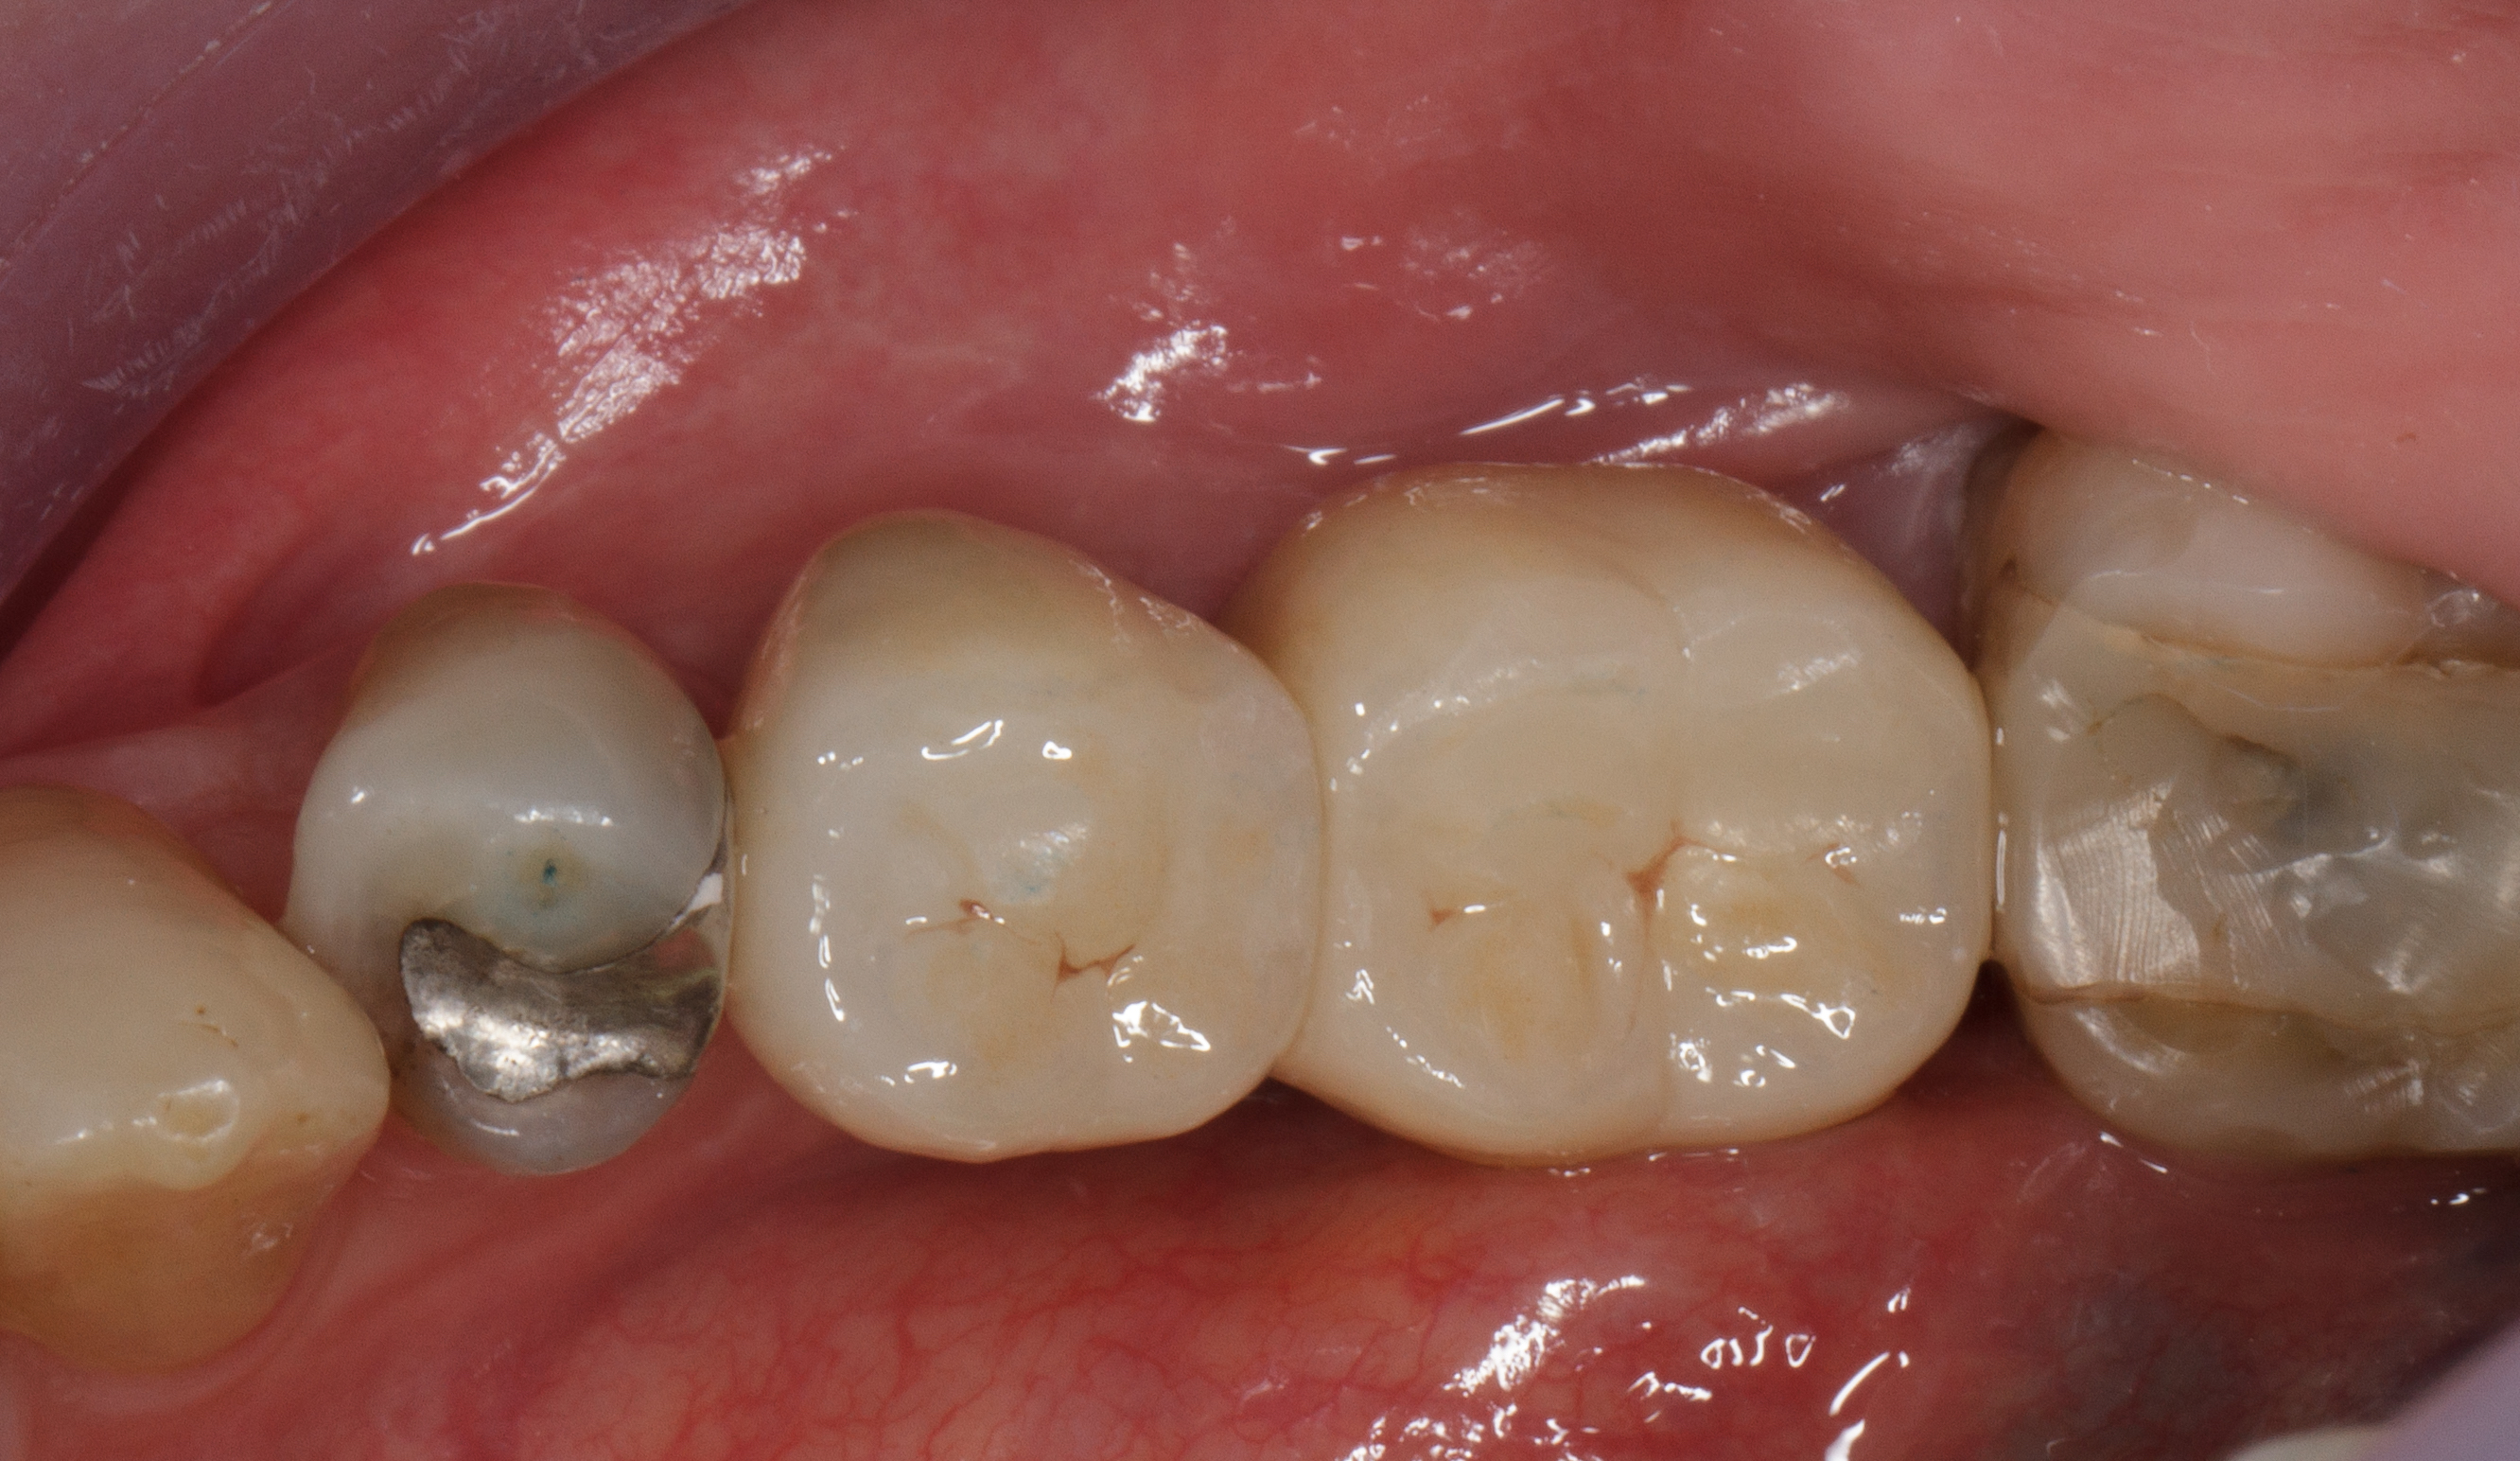

Dopo circa sei settimane si è formata una ampia banda di tessuto cheratinizzato perimplantare che facilita una adeguata igiene orale e da protezione al tessuto osseo sottostante (Figure 27-28).

Vengono cementate due corone in zirconio stratificato (Figura 29). Il controllo clinico e radiografico dopo 18 mesi mostra la buona risposta dei tessuti gengivali e la stabilità ossea perimplantare (Figure 30-31).